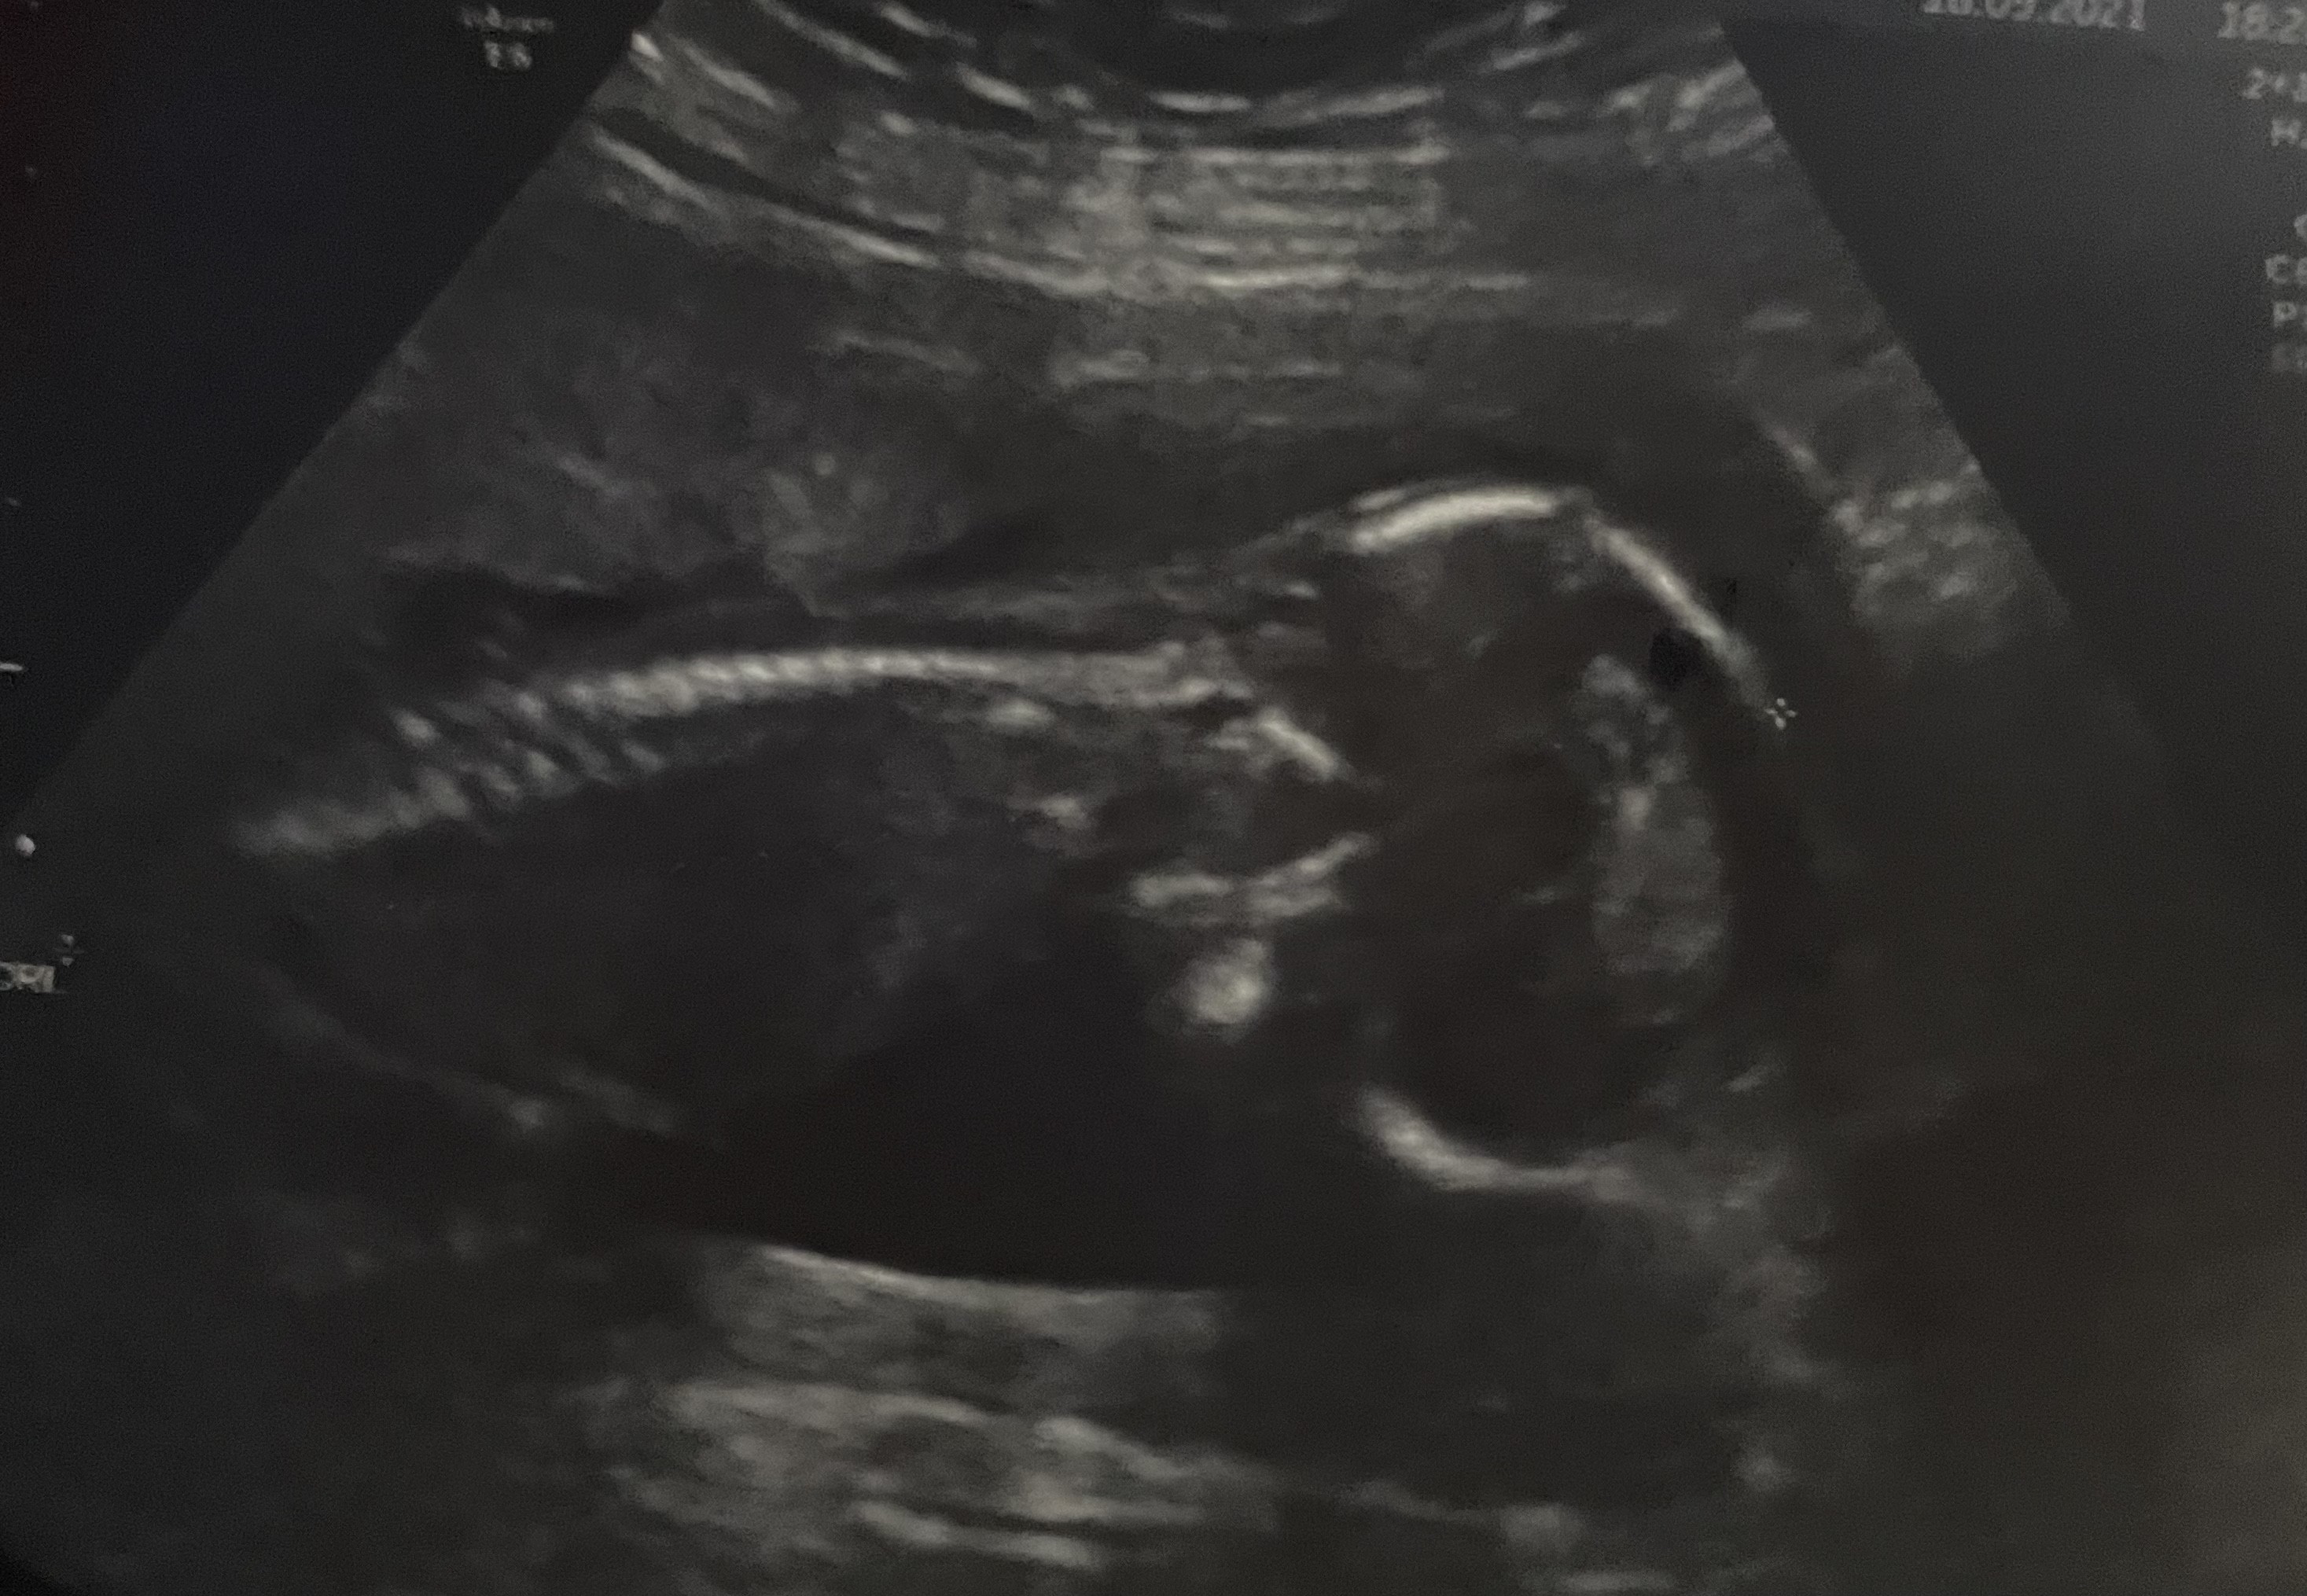

Chłopiec czy jednak dziewczynka ?

Czy tu napewno chłopiec ?

Dzięki za odpowiedz ,a czemu tak myślisz coś ci mówią zdjęcia?Mam usg połówkowe za 3 tygodnie to pewnie lekarz potwierdzi 😊

Bo jakoś z tego pierwszego zdjecia widać że.cos odstaje jakby pępowina. Nie wiem czy to może nie napuchniete wargi sromowe, ale to takie gdybanienie. A na tym ostatnim zdjęciu to tak jakby ten wyrostek był płaski na dziewczynkę.